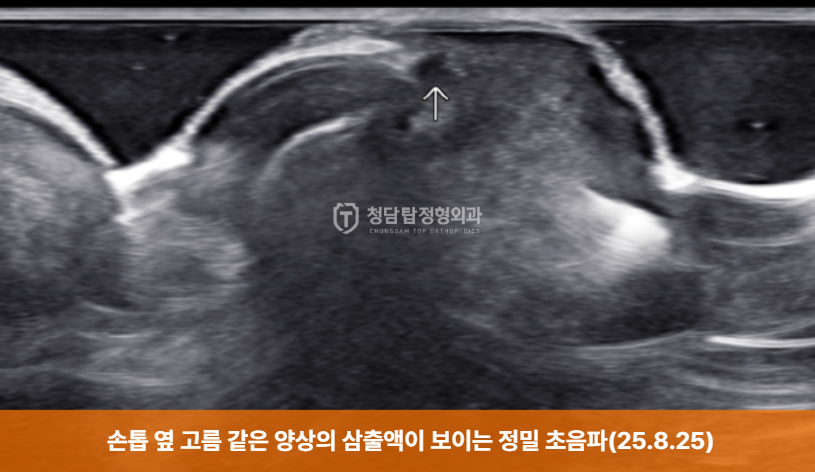

조갑주위염의 정확한 진단을 위해 정밀 초음파 검사를 시행했습니다.

초음파 검사 결과, 손톱 옆 피부 아래에 고름과 같은 삼출액이 고여 있는 것이 확인되었습니다.

이처럼 초음파 검사는 염증의 정도와 고름(농양) 형성 여부를 정확히 파악하여

손톱 거스러미 염증의 치료 방향을 결정하는 데 중요한 역할을 합니다.